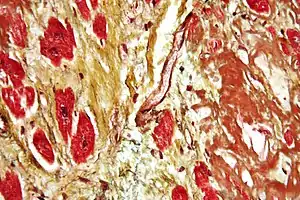

Histopathology

Histopathology refers to the microscopic examination of various forms of human tissue. Specifically, in clinical medicine, histopathology refers to the examination of a biopsy or surgical specimen by a pathologist, after the specimen has been processed and histological sections have been placed onto glass slides.[16] This contrasts with the methods of cytopathology, which uses free cells or tissue fragments. Histopathological examination of tissues starts with surgery, biopsy, or autopsy. The tissue is removed from the body of an organism and then placed in a fixative that stabilizes the tissues to prevent decay. The most common fixative is formalin, although frozen section fixing is also common.[17] To see the tissue under a microscope, the sections are stained with one or more pigments. The aim of staining is to reveal cellular components; counterstains are used to provide contrast. Histochemistry refers to the science of using chemical reactions between laboratory chemicals and components within tissue. The histological slides are then interpreted diagnostically and the resulting pathology report describes the histological findings and the opinion of the pathologist. In the case of cancer, this represents the tissue diagnosis required for most treatment protocols.